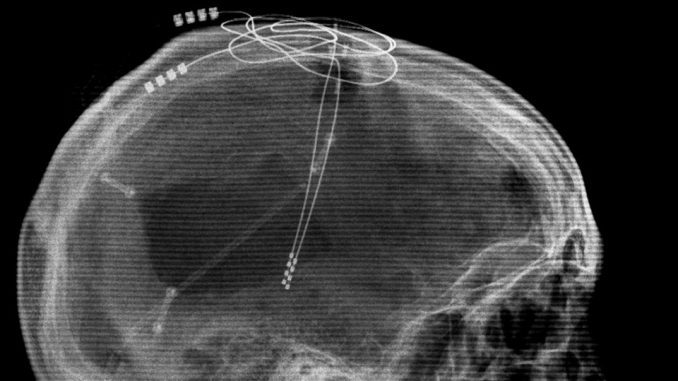

In a recent study published in The Lancet, the researchers of Toronto’s Krembil Neuroscience Centre attempted to try and stimulate an area of the brain called the corpus callosum, which is apparently a thick bundle of nerve fibres dividing the left and right sides of the brain. The area is already being used for deep stimulation to treat patients with depression. The research enlisted six women as recruit, who were suffering from anorexia nervosa, between 4 and 37 years and implanted electrodes into their brains.